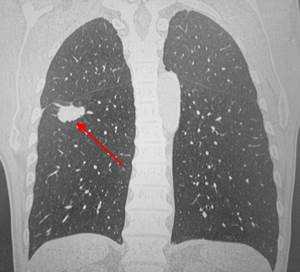

Периферический рак легких на КТ выглядит как очаг либо узел, расположенный на периферии органа вдалеке от корня. Обычно он имеет однородную структуру, в некоторых случаях с участками некроза, обызвествлениями и кровоизлияниями в паренхиму. Края типичной раковой опухоли неровные, с множественными «спикулами» за счет лимфангиита. При расположении вблизи плевры образование деформирует ее и подтягивает к себе. Размеры его различны - от очага (3-10 мм) до узла (10-50 мм и больше).

Типичный периферический рак легкого (аденокарцинома) на МСКТ. Справа в 6 сегменте легкого выявлен плотный мягкотканный узел со спикулами, деформирующий и подтягивающий к себе междолевую плевру.